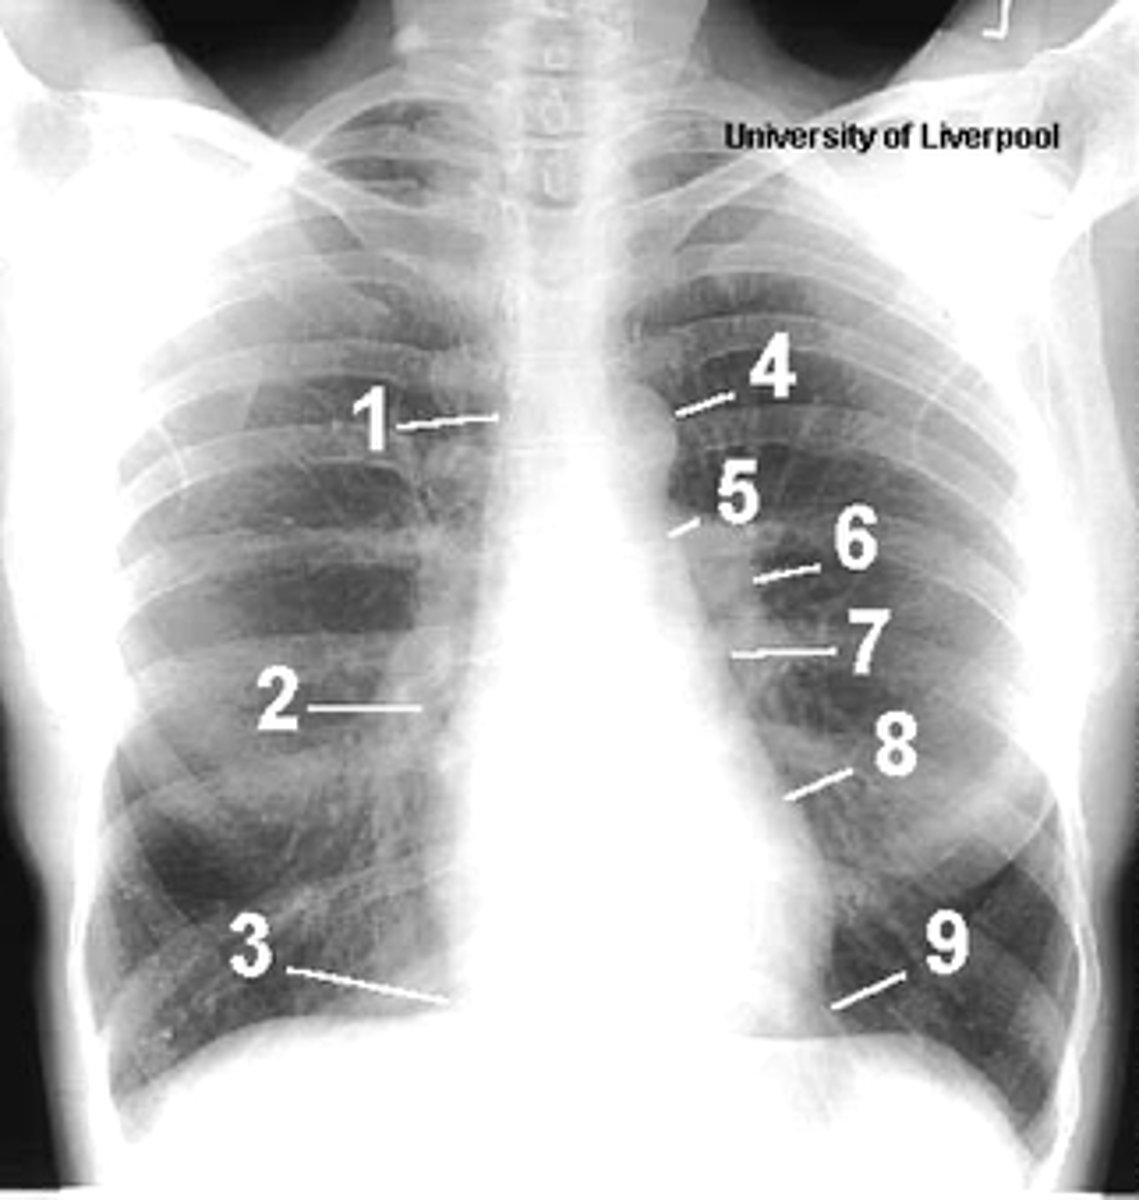

1

superior vena cava

2

right atrium

3

inferior vena cava

4

aortic arch or knob

5

left pulmonary trunk

6

left pulmonary artery

7

left atrium

8

left ventricle

9

left cardiophrenic angle